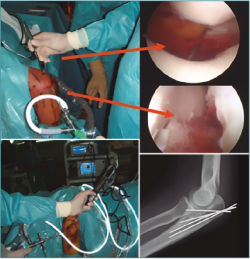

Las fracturas I y II pueden tratarse con una técnica asistida por artroscopia mediante una reducción cerrada, fijación inicial con 1 AK y fijación retrógrada con el uso de 1-2 tornillos canulados (Figuras 3 a 6).

Figura 3. Fractura de capitellum: reducción cerrada, colocación y portales.

Figura 4. Fractura de capitellum: colocación de 2 tornillos canulados.

Figura 5. Control radiográfico de fractura de capitellum asistida por artroscopia.

Figura 6. Resultado a los 2 meses de fractura de capitellum asistida por artroscopia.